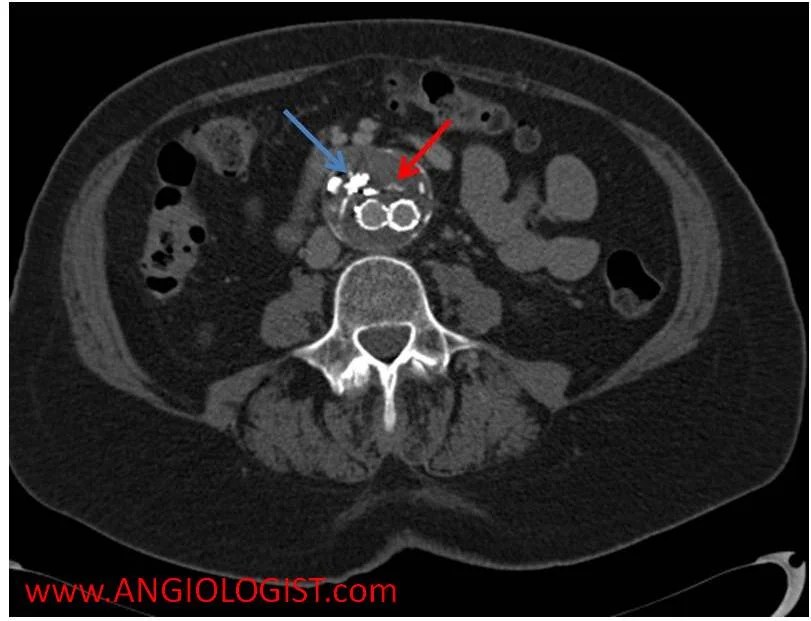

Endoleak an endoleak is the leaking of blood outside a stent graft and within an aneurysm sac By grasping the nuances of these types, individuals and healthcare professionals can better comprehend the condition and make informed decisions about its management.

It’s a common complication of endovascular aneurysm repair (evar) Causes & management firstly, let’s understand the classification system used to categorize endoleak types There are five types of an endoleak

Endoleaks may require endovascular treatment methods to prevent aneurysm rupture. Open surgery is an alternative for individuals who cannot be treated successfully with less invasive techniques Type iv endoleak a type iv endoleak often resolves on its own, once blood clotting has normalized. An endoleak is a leak of blood into the aneurysm sac after an endovascular aneurysm repair (evar) procedure

Learn about the five types of endoleaks, how they are diagnosed and treated, and why they can be dangerous. An endoleak is a complication of endovascular aneurysm repair (evar) where blood leaks into the aneurysm sac, increasing the risk of rupture Learn about the various types and how they are diagnosed and skillfully treated at tampa general hospital. Endoleaks are characterized by persistent blood flow within the aneurysm sac following endovascular aneurysm repair (evar)